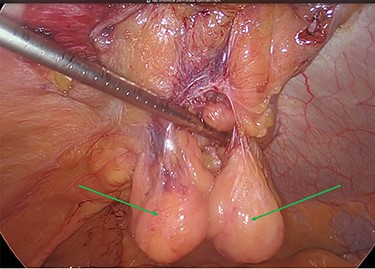

The viable omentum was reduced into the peritoneal cavity. Two lipomas were then observed attached to the parietal peritoneum (Figs 3 and 4). The lipomas were also reduced into the peritoneal cavity from within the hernia sac. Each one was 2 cm in diameter based on laparoscopic visualization using the 1 cm markings on a suction irrigation device.

The two peritoneal lipomas (green arrows) and the visible umbilical hernia neck (blue circle). Intracorporeal suturing of the hernia neck (green arrow) and closure of the hernial defect.